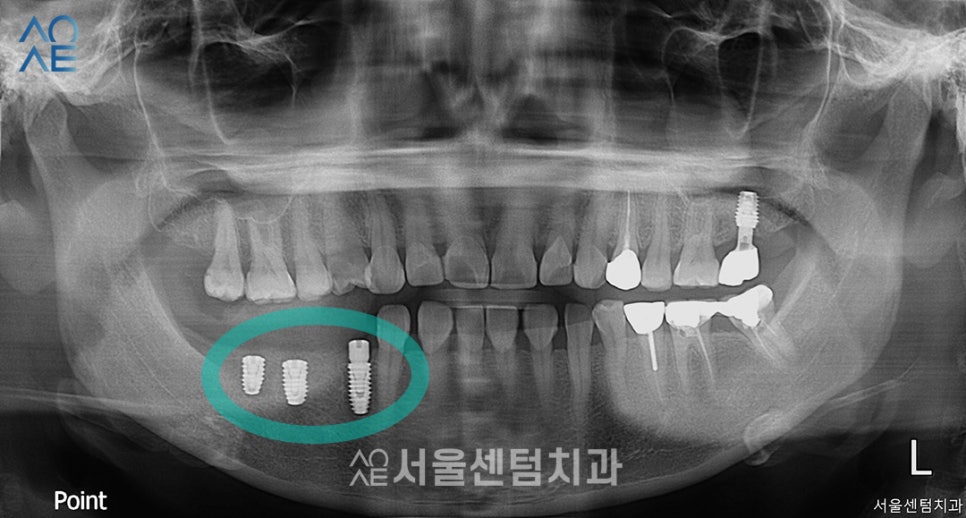

위 사진은 식립 직후 촬영한 엑스레이입니다.

안정적인 깊이와 방향으로 잘 식립된 모습이 확인됩니다.

사진상으로 왼쪽 2개가 큰 어금니

오른쪽 1개가 작은 어금니용입니다.

다음날 소독을 진행하고

한달 뒤 경과를 꼼꼼히 체크하였습니다.

환자분께서도 크게 불편함 없으시다고 하셨습니다.